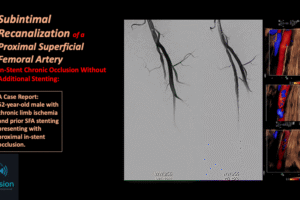

Angiography - Coronary Artery - MRI

Angiography - Supraaortic Trunk - Vascular Echodoppler